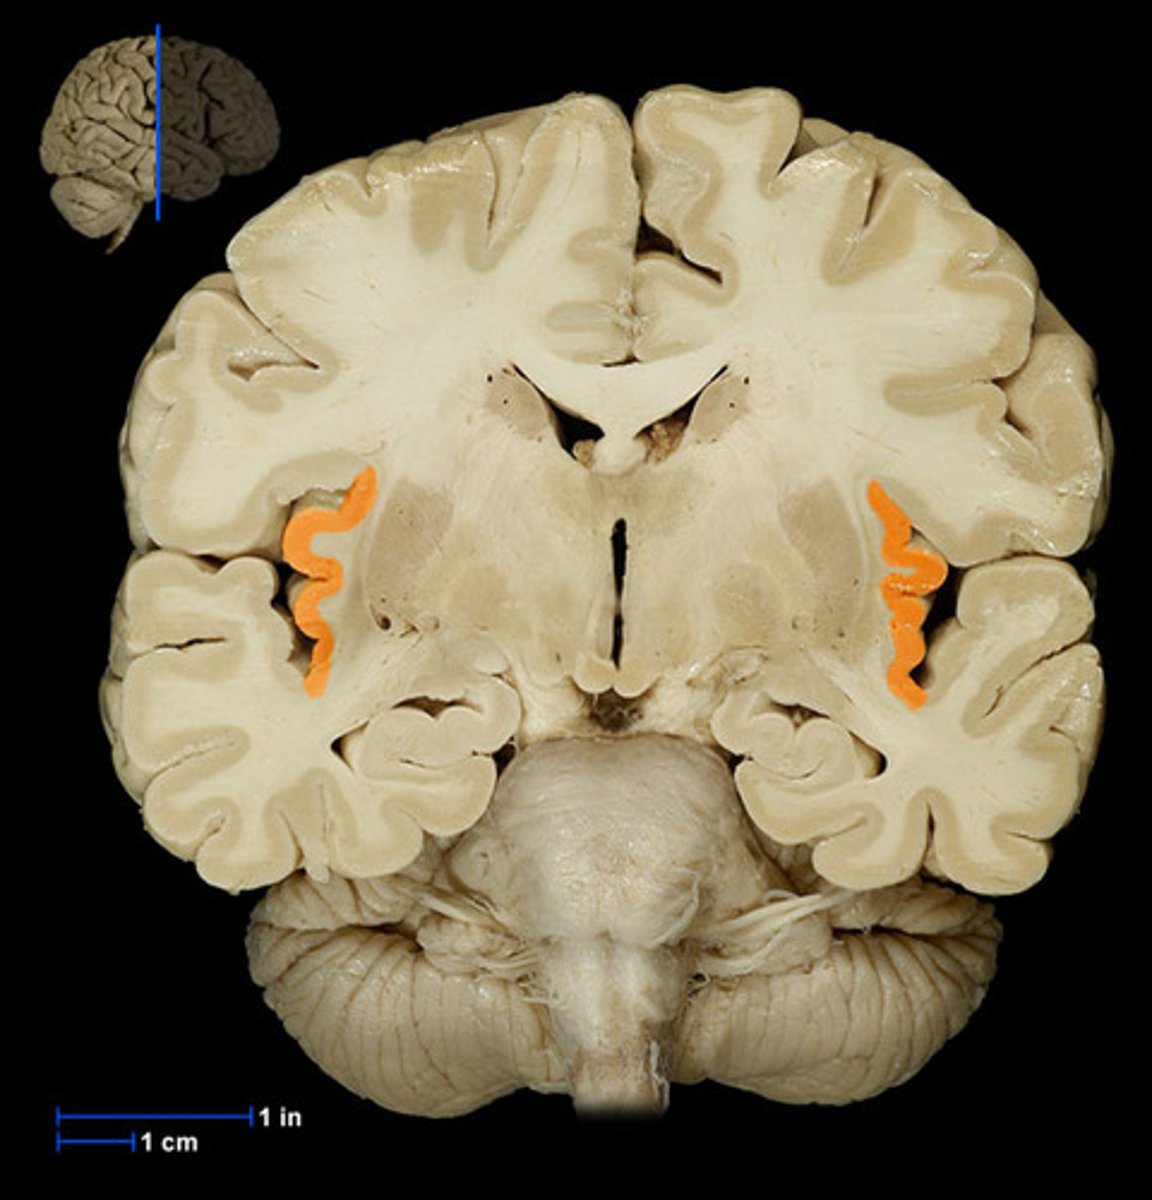

what are the 3 regions of the brain?

1. cerebrum (cerebral hemispheres)

2. brainstem

3. cerebellum

what are the 4 main lobes of the cerebrum?

FPOT

1. frontal

2. parietal

3. temporal

4. occipital

which layer of the cerebrum is the outer gray matter?

cerebral cortex (composed of neuronal cell bodies)

which layer of the cerebrum is the inner layer containing myelinated fibers and associate neuroglial cells?

subcortical white matter

which layer of the cerebrum makes up the basal ganglia and the limbic system components?

subcortical gray matter